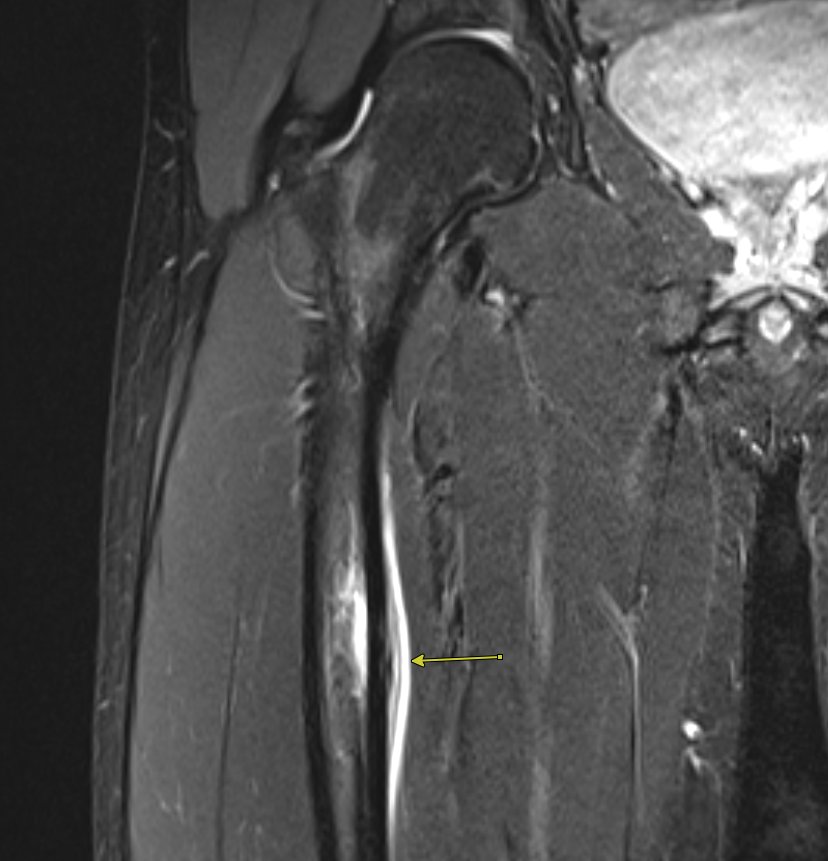

1 Coronal T2 fatsuppressed MR image in a 40yearold runner with hip Endosteal And Periosteal Edema the continuum of findings ranges from periosteal edema (grade i), to both periosteal edema and marrow edema seen on. It’s typically the response to an injury or a condition like osteoarthritis. bone marrow edema is a buildup of fluid in the bone marrow. this can be seen in osteoarthritis in bone under areas where cartilage is damaged;. Endosteal And Periosteal Edema.